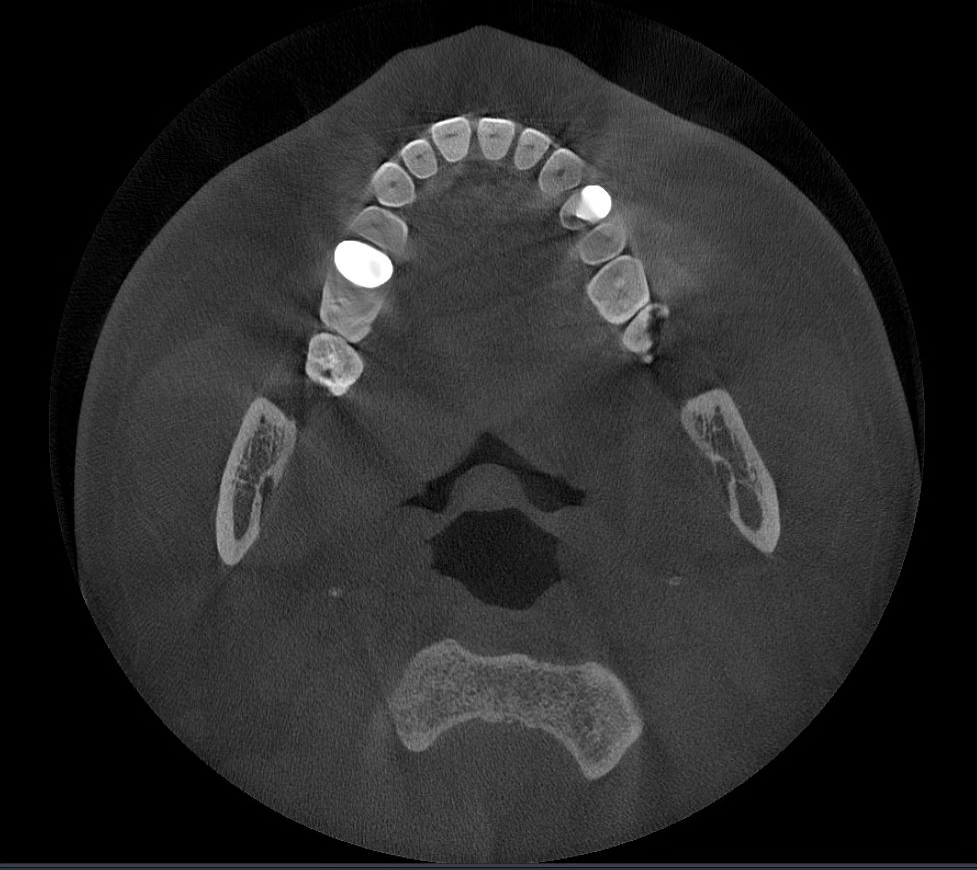

Các hiện vật kim loại được xóa bằng công nghệ AI và cấu trúc răng, mão kim loại và cấy ghép được phục hồi chính xác dựa trên các nguyên tắc toán học.

MAR cũ